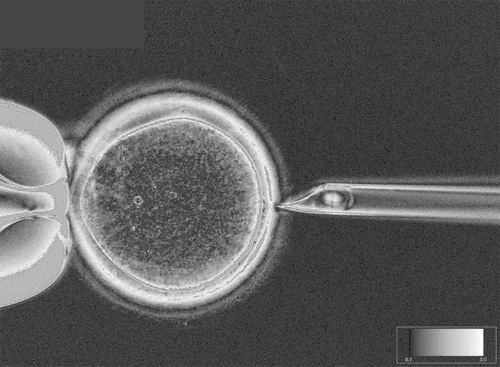

研究人员发明了转换卵细胞基因材料的方法,用拥有健康线粒体的卵细胞取代携带错误线粒体DNA的卵细胞。结果是,胚胎会携带来自母亲和父亲的核DNA,以及卵细胞捐献者的线粒体DNA。